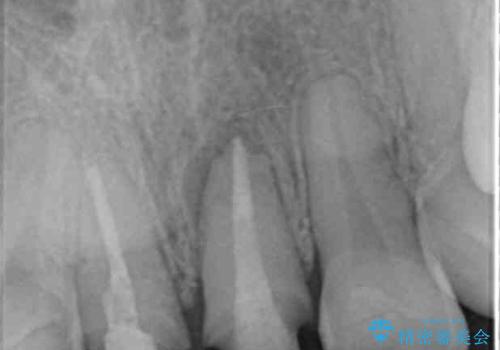

歯ぐきを押すと痛い、うずく、響く、などの症状は感染根管による根尖性歯周炎や歯の破折の所見であることが多々見られます。

今回は根尖性歯周炎に対する根管治療を行ったことで症状は改善し、快適に食事ができる状態へと改善しました。